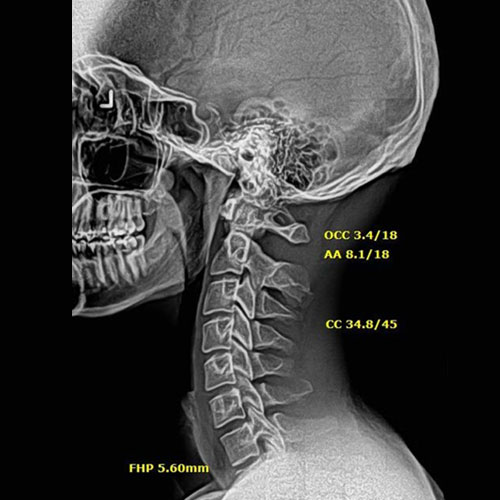

After Corrective Chiropractic Care: Following a customized course of corrective chiropractic treatment, repeat X-rays demonstrated measurable improvement in cervical alignment. More importantly, those structural changes translated into real-life results — reduced pain, improved function, and a return to daily activities with confidence.

This is the difference between symptom-based care and corrective care.